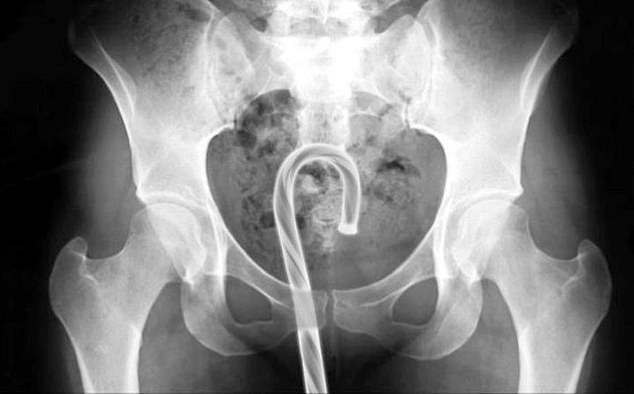

漢恩和另外一名醫師,就曾經處理過下體被塞進雪人模型、聖誕樹模型等病例,甚至有病患是直接把大型「聖誕老人摩杖棒棒糖」塞進下體,然後拔不出來。另外漢恩也處理過,巴斯光年玩偶被塞進下體、拔出不來的狀況。

醫師群也表示,通常醫師遇到下體有異物的狀況,最先的處理方式會試圖用「自然取出法」,也就是「異物怎麼被放進去,就怎麼樣拿出來」。但若真的用徒手或自然方式取不出來的話,就只能開刀解決。醫師說,異物被塞進下體後,有可能造成直腸或其他器官破裂,甚至進一步變成出血或感染,相當危險,因此呼籲民眾們真的不要亂玩下體。